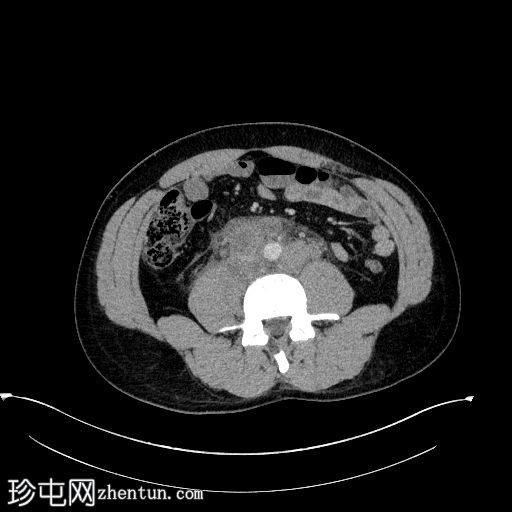

轴向 C+ 门静脉期

腹膜后淋巴结肿大,包括一些坏死淋巴结,高度怀疑有淋巴结转移。